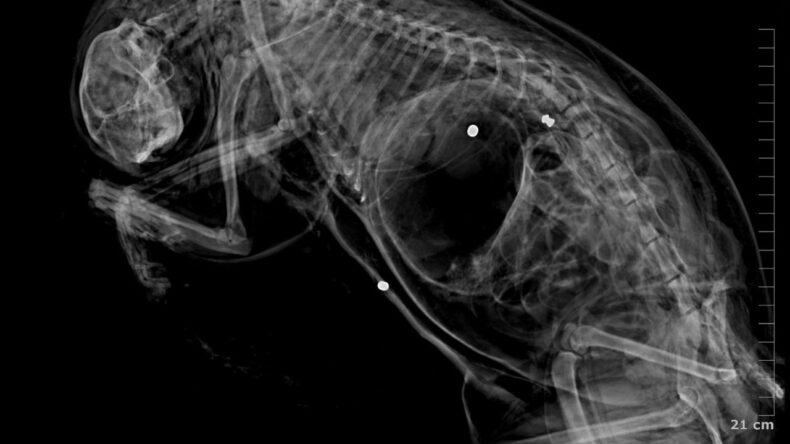

Klinik raporunda, 'ateşli silah yaralanması ile uyumlu patolojiler' tespit edilmesi, hayvanların tüfek mermisi ile öldüğüne dair bulguların bulunduğu ifade edildi. Bülbül, güvenlik kamera görüntülerinden komşusu K.G.'den şüphelenmeye başladı. Görüntülerde K.G.'nin bahçesine giren bazı kedilerin birden kaçtığı gözlemlendi.

K.G.'nin kedileri bahçesinde av tüfeği ile vurduğunu belirten Ürkmez, “Buna dair delilleri dosyamıza sunduk. Ayrıca, veteriner ön raporunda da kedilerin ölümünde mermi parçalarına rastlandığı açıkça belirtilmiştir. Kamera kayıtlarını da delil olarak sunmuş bulunmaktayız. '5199 sayılı Hayvan Haklarını Koruma Kanunu' kapsamında şüphelinin ceza alması için her türlü çabayı göstereceğiz. Nihai kararı mahkeme verecektir. Şüphelinin yurtdışına çıkışı ve adli kontrolü devam etmektedir” ifadelerini kullandı.